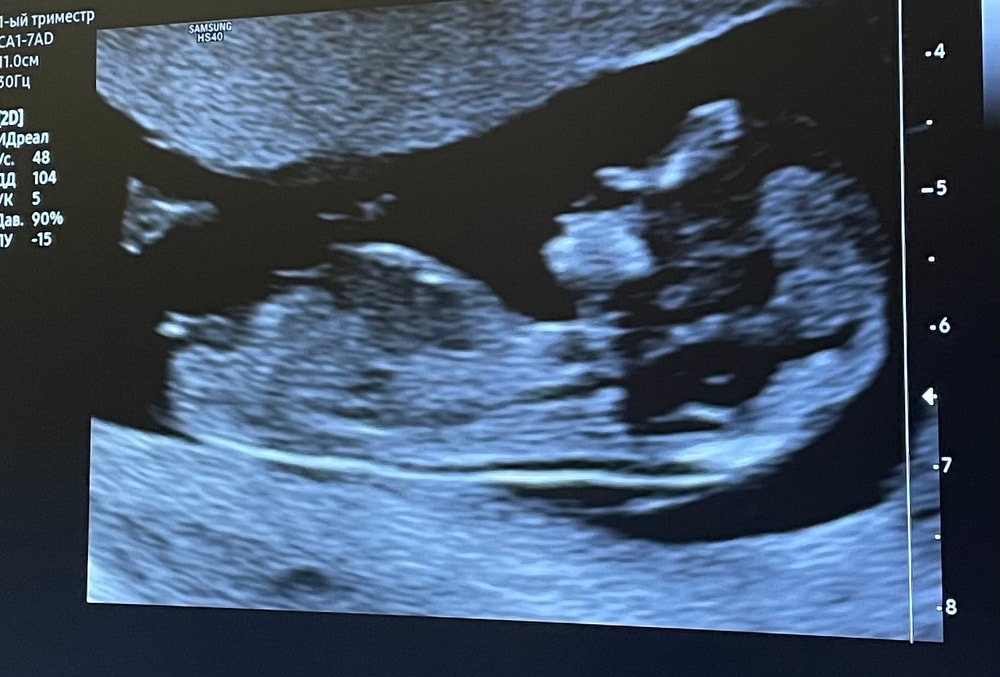

Есть теория, что пол ребенка на 1 скрининге можно определить по половому бугорку.

Врач видит предположительно девочку (смотрели снизу), кто на фото по вашему мнению?!